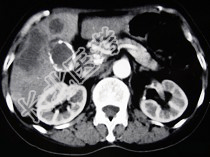

- 单项选择题女,66岁, 右上腹痛,发热伴有黄疸两月余, 消瘦、纳差,影像检查如图, 最可能的诊断为( )

A、胆囊癌及原发性肝癌

B、肝内胆管细胞癌

C、胆囊结石及脂肪肝

D、胆囊结石及肝血管瘤

E、胆囊癌肝转移